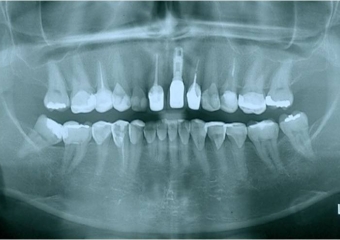

Raio X com implante instalado

Raio X final